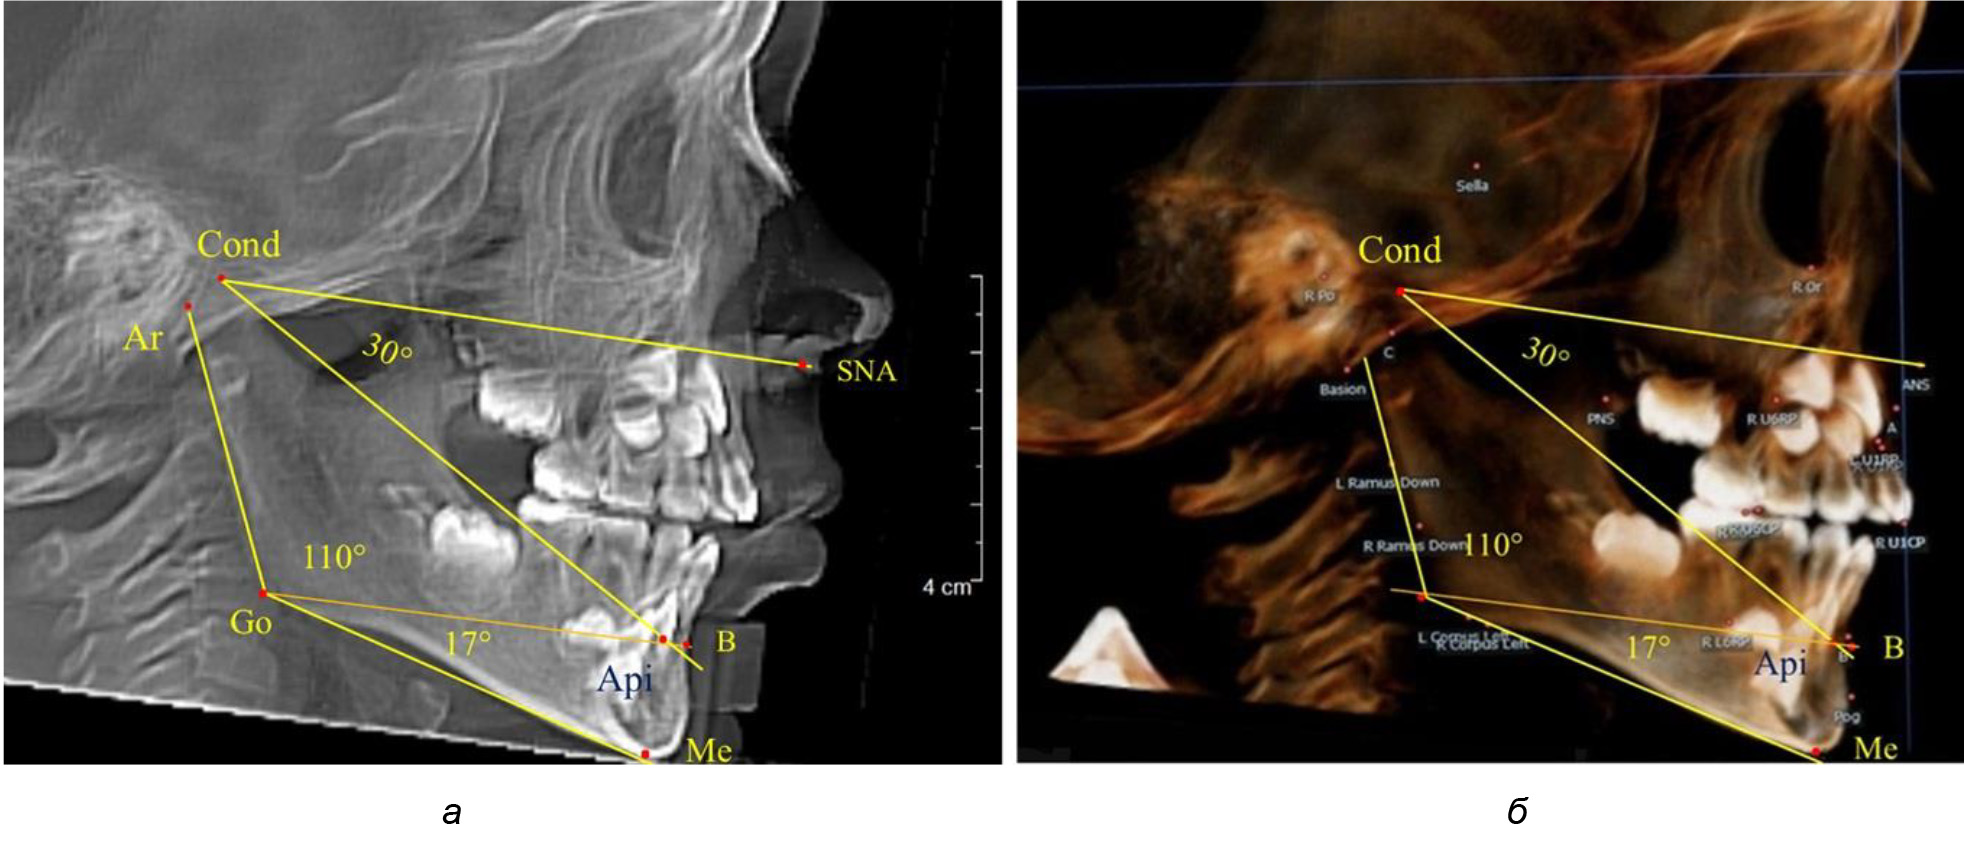

Особенность анализа телерентгенограммы в периоде сменного прикуса заключалась в том, что наслоение зачатков постоянных зубов затрудняло определение апикальной точки нижнего резца. В подобных случаях использовали метод совмещенного анализа телерентгенограммы с фрагментом томограммы, на котором, также как и на телерентгенограмме, определяли положение резцовой и апикальной точек с построением условной вертикали, которая служила ориентиром для совмещения фрагментов (рис. 2).

Рис. 2. Особенности совмещения телерентгенограммы с фрагментом томограммы в сменном прикусе